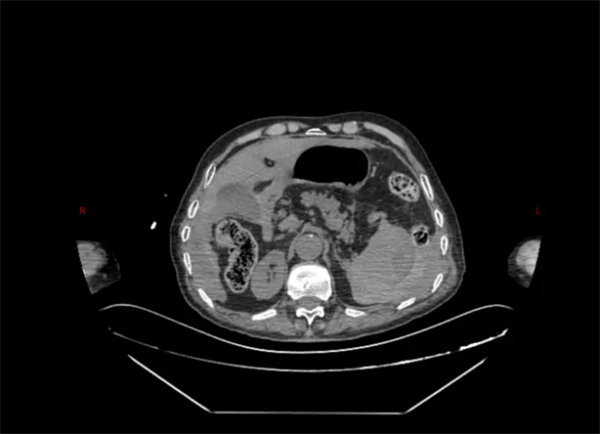

急診行CT檢查提示:脾臟密度不均勻升高,考慮脾破裂。在就診過程中,患者逐漸出現心率增快,血壓降低,行腹腔穿刺抽出不凝血,結合患者既往病情及輔助檢查,考慮脾破裂可能性極高。患者病情危重,醫院立即啟動綠色通道,急診科、肝膽胰脾外科、麻醉手術科等科室共同協作,將病人由急診搶救室直接轉運至手術室急診手術治療。

術中,探查可見患者脾臟包膜下巨大血腫并包裹脾臟,包膜表面可見裂口,并伴有活動性出血,考慮遲發性脾破裂。由于患者年齡較大,必須盡量將手術時間縮短,否則隨著手術時間的延長,患者術中術后出現麻醉風險及各類并發癥的可能將大大增加。然而,脾臟周圍密布著脾動脈、胃短動脈等各式各樣的血管,如同布滿引線的火藥庫,想要快速、精準分離脾臟周圍組織與血管更是難上加難,任何1毫米的偏差都可能引發難以控制的大出血。患者在術前已經出現休克征象,如果術中再次出現出血等情況,極有可能造成難以挽回的結果。科主任金上博與副主任張曉賓通力合作,憑借高超的手術技術及豐富的手術經驗,不到1小時即完成脾臟的切除,整個手術過程也僅僅用時1小時余。術中患者生命體征穩定,病人平穩完成手術。